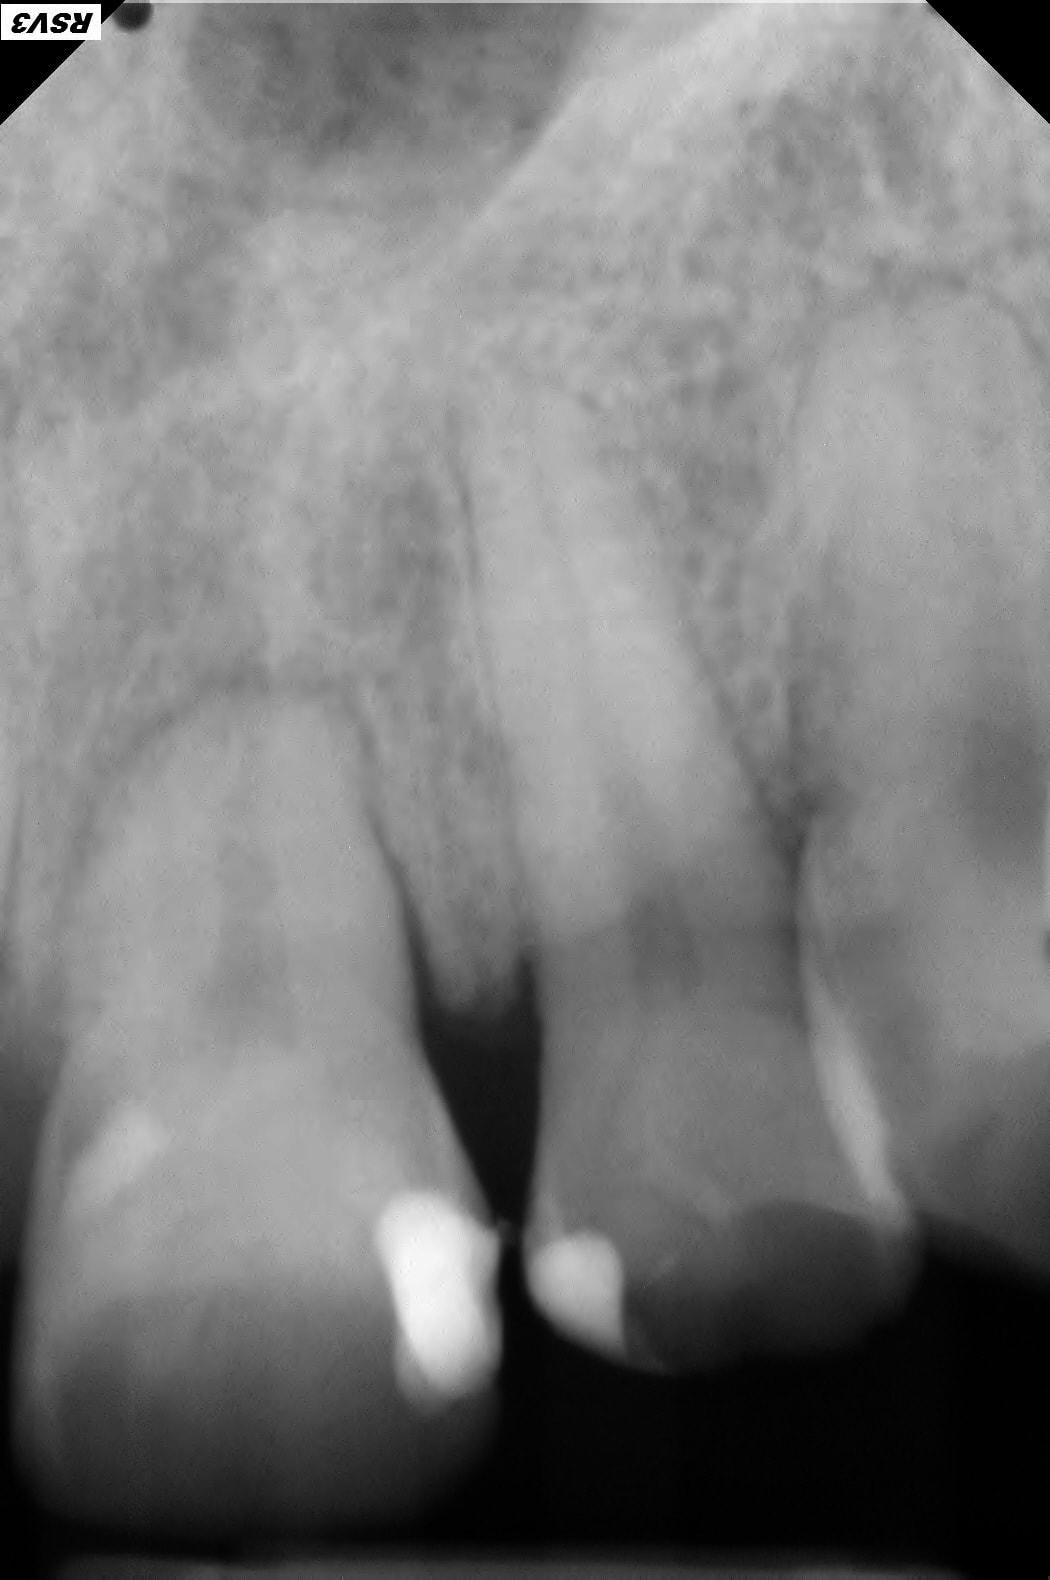

Patient 40 ans , fumeur, ex fan du coca, stressé, bruxomane forcené qui présente des érosions et abrasions chimiques généralisées.

Suite l'abrasion des dents postérieures il a une surcharge sur 11 et 21 qui sont devenues mobiles avec en plus des racines résorbées.

L'élargissement ligamentaire + images apicales (?) pourraient peut être expliquer la mobilité..

Elles sont bien angulées tes RX sur 11-21?

1/ Toutes les dts st abrasées, pas ou peu de déchaussement gingival et mobilité des incisives sup, pas de résorption radiculaire plutôt une arthrite ligamentaire. Pronostic de perte des incisives engagé à moyen terme.